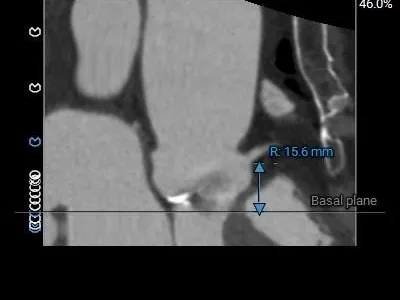

LCA Height

RCA Height

冠脉开口高度尚可,瓣叶切线测量距离<冠脉开口下缘到根部距离,结合瓦氏窦及STJ预估低冠脉风险;

瓣环水平夹角44°,非横位心,弓角、弓距可,预估输送器可顺利过弓、跨瓣;

手术策略制定

经CT测量该患者瓣环仅为20.2mm,属于极小瓣环。小瓣环AS病例在进行TAVR治疗时往往面临更多技术挑战如术中即刻冠脉风险、术后PPM发生可能、未来冠脉再介入难题、远期TAVR-In-TAVR窦隔离问题。考虑该患者TAVR术后PPM发生率较高,需要为其挑选一款成形较好、能够提供更大瓣口面积的瓣膜,如环上瓣类型、直筒状类型、自膨式类型的瓣膜。经团队讨论决定选用全可回收自膨短瓣ScienCrown系统进行植入。